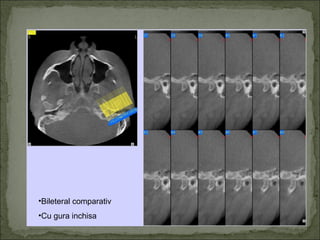

•Bileteral comparativ

•Cu gura inchisa